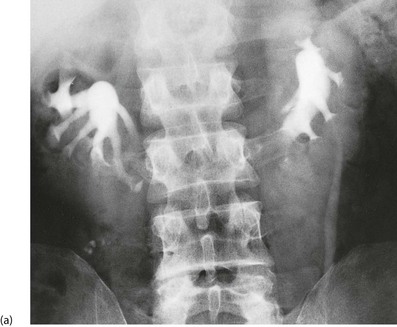

Fig. 39.3 Duplex systems

(a) Partial and total duplication. In a total duplex system (right), the ureter from the upper renal moiety may open into the urethra or vagina (i.e. wholly ectopic). Such an ectopic ureter causes continuous incontinence and presents early in life. Otherwise, it opens inferiorly in the bladder (centre). The orifice is often stenosed and a ureterocoele results (dilated lower end of ureter). Vesicoureteric reflux often occurs via the upper ureteric orifice back into the lower renal moiety.

(b) Duplication of the ureters on the right side; only one ureter can be seen passing as far as the bladder. The vesicoureteric junction is associated with a small, elongated ureterocoele (arrowed)

The ureter draining the lower moiety may have a defective distal antireflux mechanism, predisposing to infection and renal parenchymal damage. The typical IVU picture is of calyces that look like a ‘drooping daffodil’.